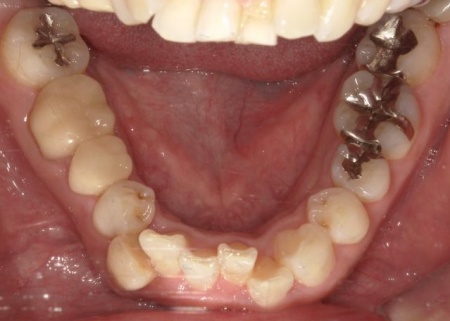

抜歯後は骨や歯茎の回復を待ち、口腔内の状態が安定した段階で、インプラント埋入手術へ進みました。

インプラントは、右上4番目と6番目の位置、左上4番目と6番目の位置に埋め込みます。

インプラントがしっかりと骨に定着したことを確認したら、精密な型取りを行い、ブリッジを作製して装着しました。

インプラント治療と併せて保存可能な歯の治療も進め、右上の一番奥の歯と右下の奥歯(前から5番目と6番目)に対して、細菌感染した神経を取り除いてから薬を詰める根管治療を行い、CAD/CAM冠という白い被せ物で修復しました。

さらに、上前歯(右上の犬歯から左上の犬歯まで)、右下の4番目の歯に対しては、虫歯治療を行っています。

最後に、痛みや違和感がないか、見た目や噛み合わせに問題がないかを確認し、治療を終了しました。